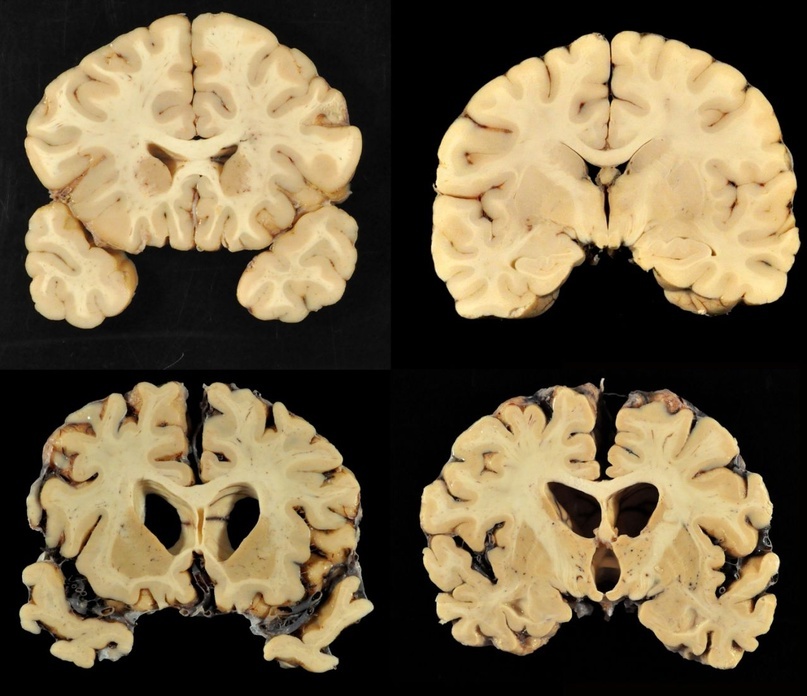

Уже давно было подмечено, что все симптомы при болезни Кройтцфельдта-Якоба подкрепляются патогистологическими изменениями. Так, при изменении моторных нейронов отмечено выпадение многих нервных клеток в двигательной области коры, включая гигантские пирамидные нейроны (клетки Беца), а также демиелинизацию пирамидных путей и утрату клеток передних рогов спинного мозга.

болезни Кройтцфельда-Якоба